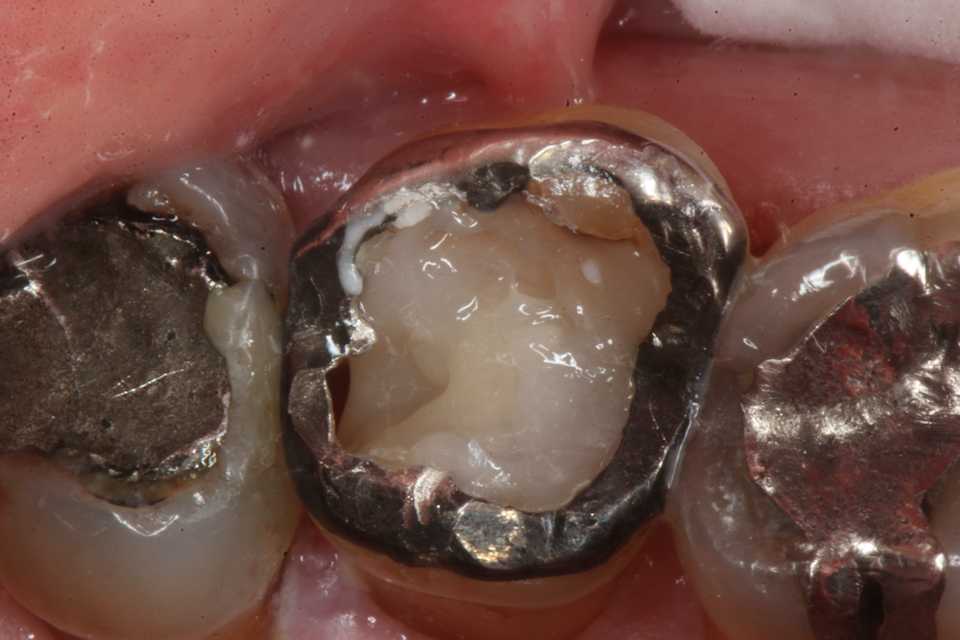

今回の実際の治療法はマージン付近の1mm幅だけは接着シロの為の健全歯質を確保し、露髄しない程度に軟化象牙質を除去し、3MIX+α-TCPで覆罩し、歯質の再硬化を期待するしかない。

再硬化力の弱い他のα-TCP以外のセメントでは失敗する可能性が高い。

では時系列でどうぞ

直視下ではこんな感じで、患部が見えないのでミラーテクニックが必要になるが、器具も届きにくいので術者も絶望的な気分になる。